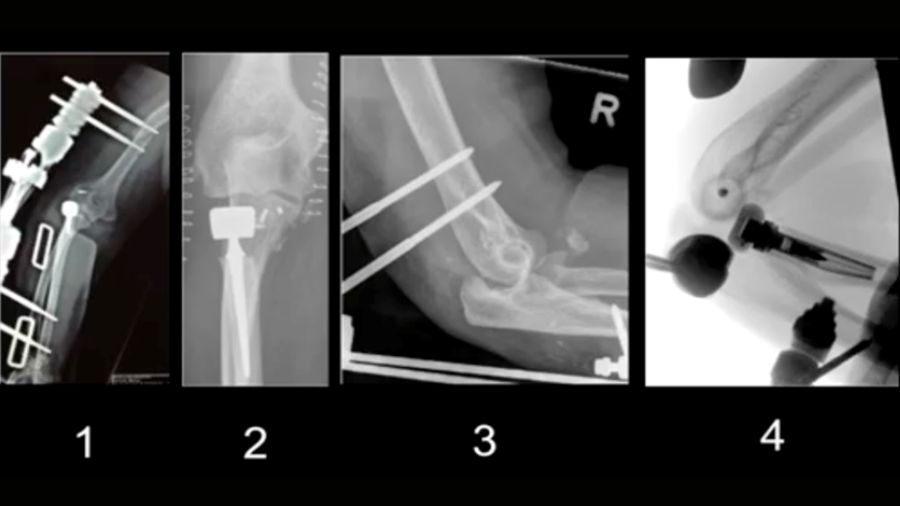

The aim of terrible triad fixation is the restoration of bony stabilizing structures (radial head and coronoid process) and lateral collateral ligament reconstruction. A surgical approach is recommended with persistent posterolateral instability following lateral collateral ligament reconstruction or when fixation of a large coronoid process fragment is indicated. The use of an external fixator is only advocated in case of persistent instability following the reconstruction of bony and ligamentous structures.

A "terrible triad" refers to a severe and complex elbow injury that involves three key elements: coronoid process fracture, radial head fracture, and elbow dislocation (either anterior or posterior). This type of injury can lead to chronic instability and complications after surgery, particularly subluxation, which is common following terrible triad fixation. Here I will demonstrate how to address post-surgery subluxation and share tips on how to identify and correct potential sources of instability during the initial surgery to avoid the need for re-operation.

Case 1: Overstuffing and medial gapping

In this case, an overstuffed radial head prosthesis led to a 1 cm elevation of the implant, causing subluxation. The video shows how to correct the prosthesis height, re-anchor the ligaments, and brace the radial head.

Case 2: 48-year-old male, fall from scaffold

A 48-year-old man presented with a luxated elbow, radial head fracture, and coronoid fracture. Despite initial surgery, a second CT scan revealed improper positioning of the radius head and a lateral shift in the elbow. Revised surgery was performed by fixing the coronoid plate and reattaching the lateral ligaments.